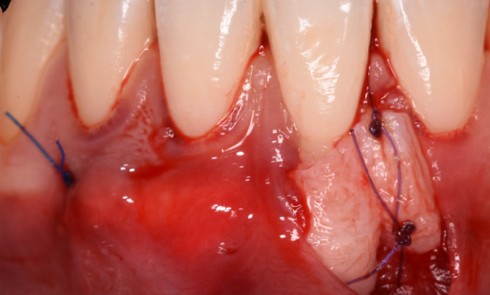

Article réservé à nos abonnés Extraction, implantation et temporisation immédiate : recycler la dent naturelle ? À propos d’un cas clinique

Les protocoles d’extraction-implantation immédiate, décrits pour la première fois en 1976 par Schulte et Heimke [1], se sont progressivement développés...